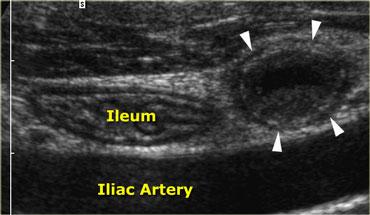

Viêm ruột thừa cấp. Ruột thừa viêm không thể đè xẹp (đầu mũi tên) nằm cạnh hồi tràng bình thường có thể đè xẹp tốt. Lòng ruột thừa giãn với đường kính 11x13mm. Lưu ý hình ảnh mức dịch-cặn bên trong lòng ruột thừa.

Hình ảnh điển hình của ruột thừa viêm là một cấu trúc hình ống dài như xúc xích, có các lớp đồng tâm, không thể đè xẹp, được xác định ở vị trí cố định tại điểm đau tối đa (Hình).

Đường kính tối đa trung bình là 9mm với biên độ dao động từ 7 đến 17mm. Trong 30% trường hợp, sỏi phân (fecolith) trong lòng ruột thừa được tìm thấy gây tắc nghẽn thực sự.